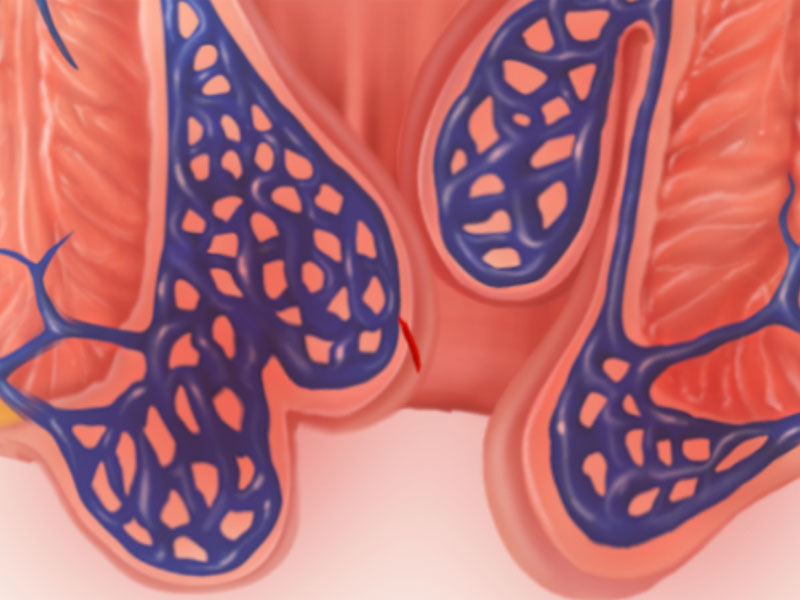

Hemorrhoids

When hemorrhoids swell, they can cause pain, bleeding, itching and soilage. Learn how to treat your hemorrhoids at home.